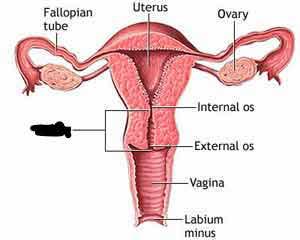

Cervix

Endometrium

Myometrium

Perimetrium

Uterine (=fallopian) tube

Uterus

Vagina

Ovary

Broad ligament

Overian ligament

Round ligament (of uterus)